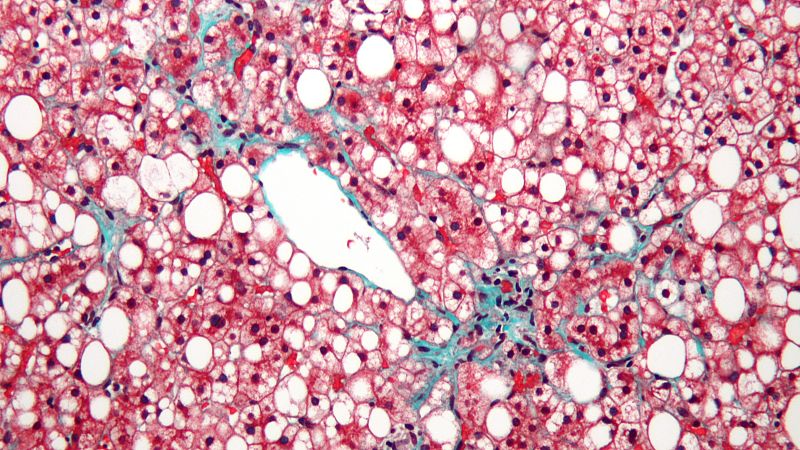

- Uno de cada diez españoles padece esta patología y la mayoría no lo sabe

- El sobrepeso es uno de los factores que más repercusión tiene en este órgano

- "Código Riñón" alerta de esta epidemia de la enfermedad renal crónica

- Este jueves 9 de marzo se celebra el Día Mundial del Riñón